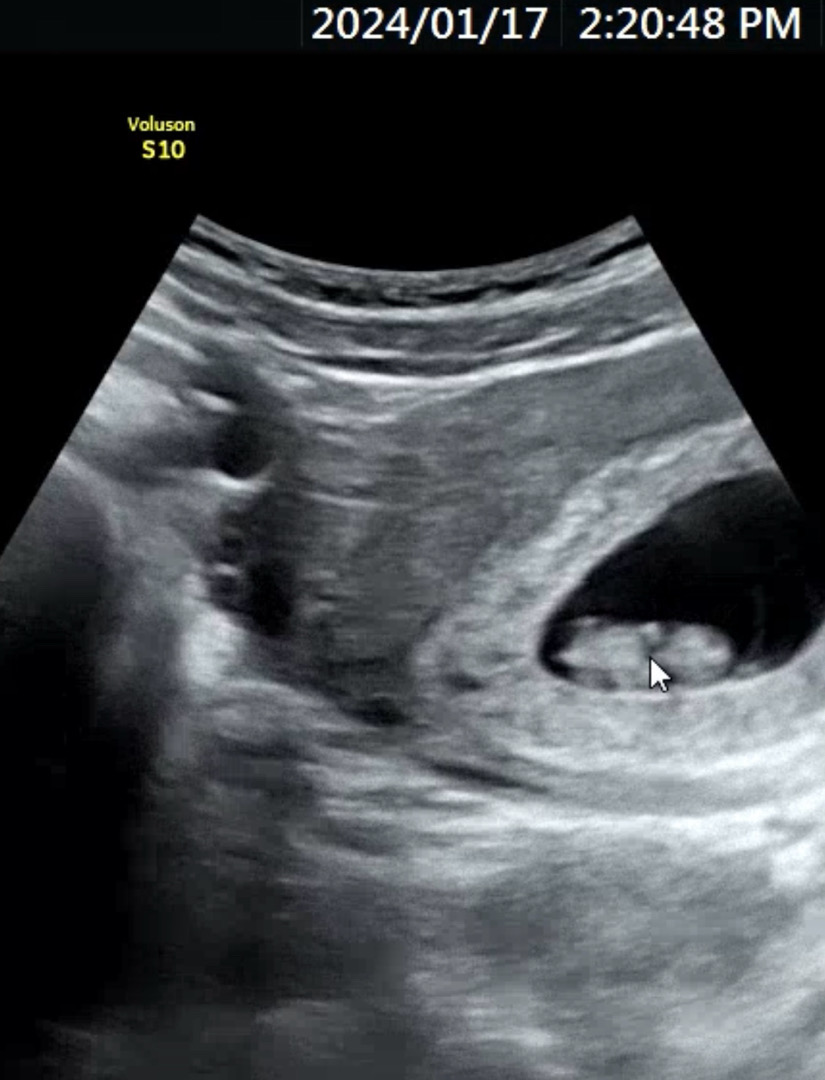

8주 5일차, 입덧을 견디며 진료 다녀왔어요! 완전 쪼꼬미 아기곰젤리가 꼬뮬꼬물 ㅋㅋㅋㅋ 잘 보니 손 발도 까궁 하고 나왔네요 ♥ 그리고 생식기 만들어지는 과정인가(?) 꼬리도 보였어요...!!! 입덧지옥에서 허우적 대고 있었는데 잠시나마 희망을 본 시간이었네요☺️